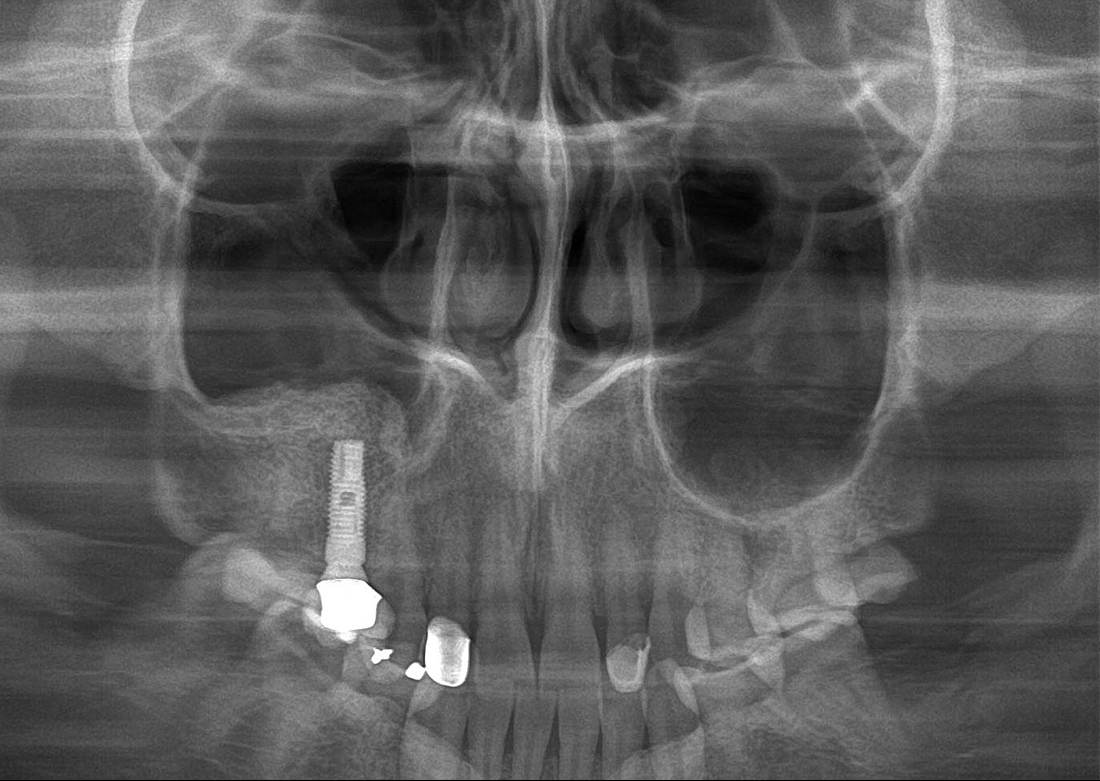

KLİNIKAI KÉPEK

Kiváló diagnosztikai képalkotás több éves tapasztalattal és szakértelemmel.

A Genoray büszkesége, amelyet világszerte elismernek és szeretnek.